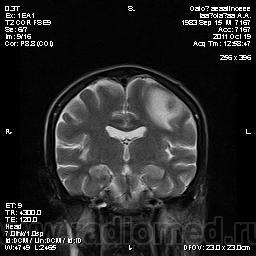

Молодой человек, жалуется только на головные боли и слабость в правой руке и ноге (около месяца).

Пациент полуасоциальный, нельзя исключить анамнез наркоманский....

ППН (включая ячейки пирамидок и сосцевидные отростки) тотально заполнены жидкостным компонентом...

Колеги, спасибо за высказывания. В данном случае про наркоманский анамнез указано не спроста... Есть мнение, что в этом лежит точка отсчета.... По поводу абсцесса и гематомы - не согласен; по поводу первого - нет соответствющей клиники, по поводу второго - не характерна локализация и сигнальные характеристики. Не буду томить общественность касательно собственного мнения. Есть две гипотезы, о которых думается в данном случае: прогрессирующая лейкоэнцефалопатия и новообразование... Но без контраста их не разрешить...